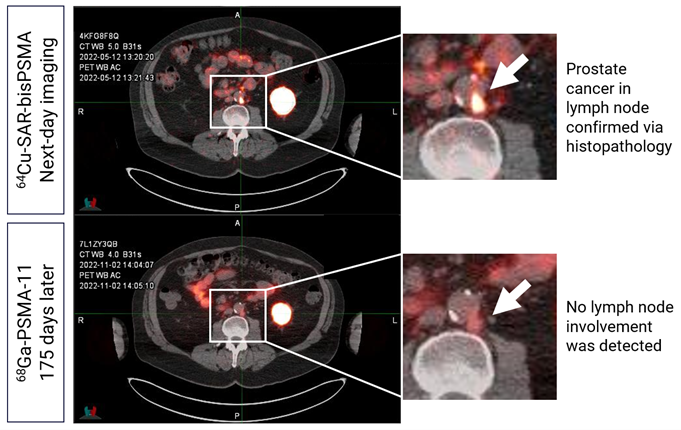

The initiation of the AMPLIFY trial is supported by compelling preclinical and clinical trial data to date, including the Phase I/II COBRA trial in patients with BCR of prostate cancer, and the Phase I PROPELLER trial in patients with confirmed prostate cancer pre-prostatectomy/pre-definitive treatment, which have been accepted for presentation or presented at leading medical conferences, including the Society of Nuclear Medicine and Molecular Imaging (SNMMI) Annual Meeting, European Association of Nuclear Medicine (EANM) Congress, American Society of Clinical Oncology (ASCO) Annual Meeting, ASCO Genitourinary Cancers Symposium and others. The data showed that 64Cu-SAR-bisPSMA is safe, and its uptake in prostate-specific membrane antigen (PSMA)-expressing cancer lesions was significantly higher compared to the approved SOC PSMA imaging agents for prostate cancer in Australia and the US. Additionally, data from the COBRA trial established that 64Cu-SAR-bisPSMA was able to detect much smaller lesions than anticipated, including a lesion with a diameter of less than 2 mm, which compares favourably against the SOC PSMA imaging agents. 64Cu-SAR-bisPSMA was also able to identify lesions months prior to these being detected by approved SOC PSMA agents (Figure 1).

Figure 1. Retroperitoneal lymph node detected by 64Cu-SAR-bisPSMA on next-day imaging. 68Ga-PSMA-11 scan performed 176 days post-Day 0 (175 days post-Day 1) did not show tracer uptake. PET/CT fusion. Prostate cancer in lymph node was confirmed via histopathology.